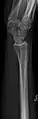

- مچ دست - DP و جانبی

تصویر مچ دست چپ به واسطه dorsoplantar

پروجکشن جانبی